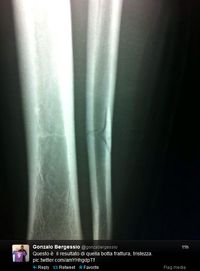

Как показал рентген, у аргентинца произошел перелом малоберцовой кости. А это значит, что Катанье придется обходиться без нападающего от двух до трех месяцев.

Ночью Гонсало в своем твиттере опубликовал рентгеновский снимок, а Кьеллини в своем микроблоге оставил следующее сообщение: